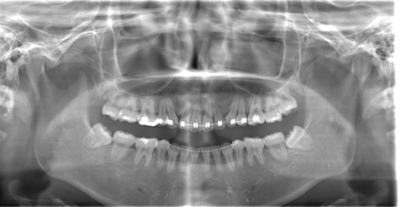

CASE 3

| 年齢・性別 | 20代・男性 |

| 主訴 | 左下親知らず抜きたい |

| 親知らずのはえ方 | 半埋伏 |

| 抜歯期間 | 30分 |

| 抜歯費用 | 約2,500円(保険内) 別途CT撮影で3,000円 |

| 抜歯内容 | 左下の半埋伏親知らず抜歯 |